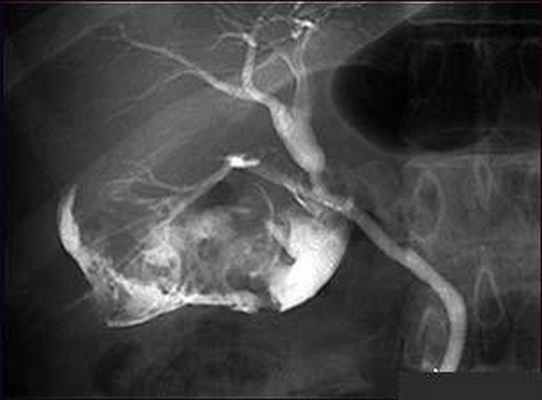

Рентгеноанатомия желчного пузыря. Для рентгенологического исследования желчного пузыря внутривенно вводят рентгено-контрастное вещество. Это вещество выделяется из крови в желчь, накапливается в желчном пузыре и на рентгенограмме образует тень, проецирующуюся на уровне I—II поясничных позвонков.